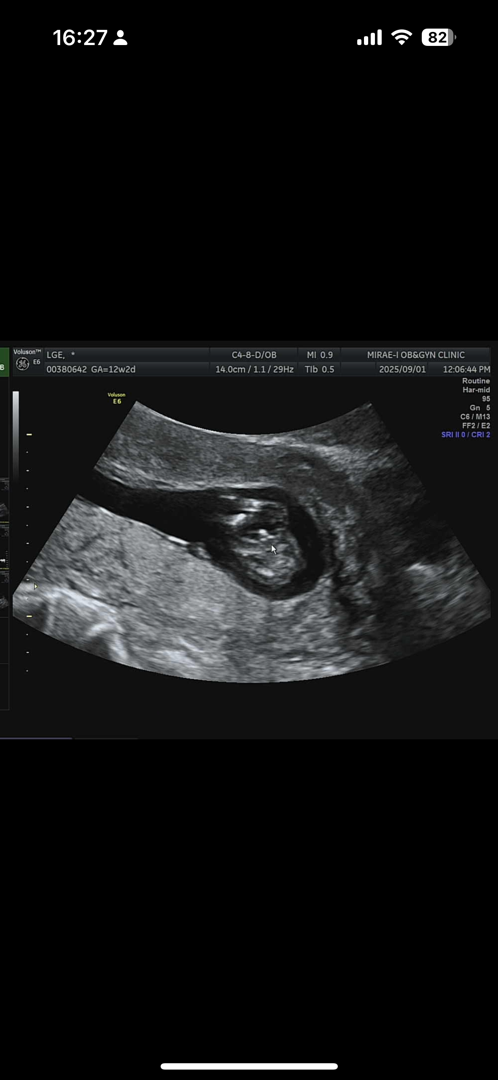

12주 니프티 하러 갔는데… 뭐가 보인다고, 60%는 아들이라고.. 모양이 너무 고추라 포기 상탭니다 하 맞겠죠? 마음의 준비가 안되었는데